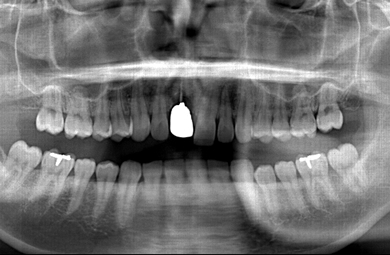

インプラントの症例写真 IMPLANT

スピードインプラント治療

| 主訴 | 上の前歯の部分の差し歯が入っているあたりが1カ月前に腫れ、他の歯科医院を受診したところ、差し歯を根から抜歯しなければならないと言われたので、インプラント治療を検討するため来院しました。 | ||||||||||||||||||||||||||||||||

| 治療方針 | 抜歯と同時にインプラントを埋入することにより、治療期間を大幅に短縮させる。 | ||||||||||||||||||||||||||||||||

| 治療内容 | インプラント1本(抜歯即日スピードインプラント)、メタルボンドセラミック1本 | ||||||||||||||||||||||||||||||||

| 総治療費 | 451,500円 | ||||||||||||||||||||||||||||||||

| 治療期間 | 5ヶ月 |